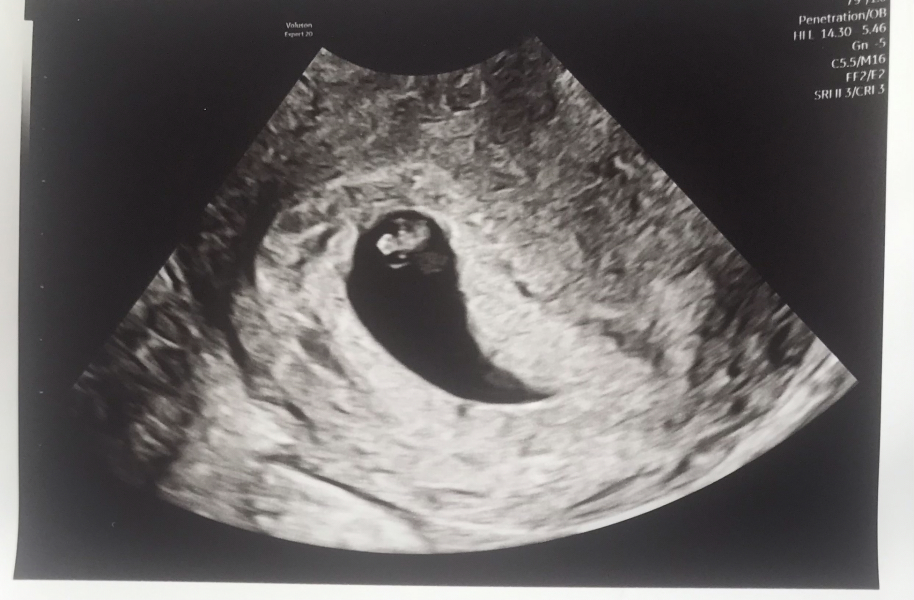

I'm still mostly laying low for a bit as we've had quite the roller coaster these last few weeks. I went for my EPU scan to confirm blighted ovum yesterday and came out with a picture of a little baby with a heartbeat. Hubs and I are still in shock and, while the EPU seemed very happy, we are guarding our hearts still. I should, going by LH, have been 7+2 yesterday, and they measured baby as 6 weeks. I'm sure of my ovulation date, so there's no chance I ovulated late. I don't really know why it could be measuring so far behind, but I know it could go either way at this point. Obviously, we are hoping for the best but trying to keep ourselves prepared for the worst

I'm in a state of limbo now and have a follow up scan with EPU in two weeks time to see if there's still a heartbeat. I've still not had any particular symptoms to speak of except some bad cramping two weeks ago and some very, very mild nausea this week. I just wanted to update everyone as I've always found this thread so lovely and supportive ❤️ Wishing you all really well.